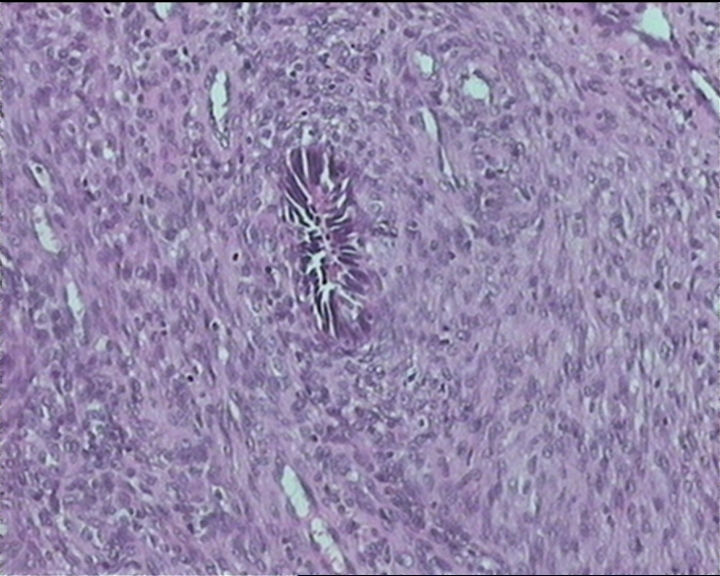

54岁女性,临床“宫颈息肉”送检;巨检:组织一块1。5*1CM,灰红。

Sternberg病理学上诊断宫颈原位腺癌的标准是腺体的上皮去粘液分化,呈乳头状或筛网状增生,核分裂易见,这例显然达不到此标准。此例还是归入到腺上皮不典型增生为好。

It is benign. Benign endocervical polyp with tubal metaplasia.

输卵管粘膜化生

细胞及腺体均有异形,图6、11、16象有纤维间质反应,考虑高级别上皮内瘤变/原位癌,腺癌不能除外。